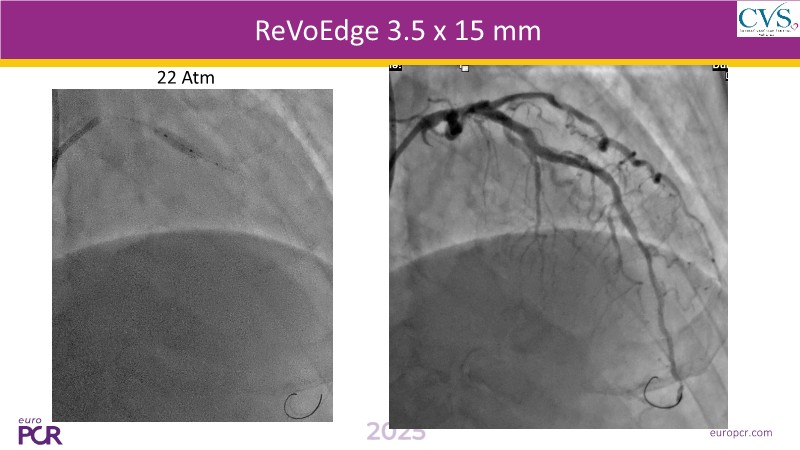

Discover how the next-generation RevoEdge high-pressure cutting balloon is transforming PCI with innovative design and proven clinical outcomes. This session presents a multicenter randomised trial and real-world case discussions, showcasing RevoEdge’s effectiveness in tackling resistant, complex lesions—including long, tortuous, and fibrotic cases. Learn practical tips, tricks, and intravascular imaging insights to optimize lesion preparation and improve patient outcomes. Don’t miss this opportunity to see how RevoEdge helps you cut through challenges and conquer PCI complexities.

- To explore the innovative design of RevoEdge: the next-generation high pressure cutting balloon

- To learn about the clinical benefits and tips and tricks of using RevoEdge high pressure cutting balloon in different types of complex lesions through case-based discussion